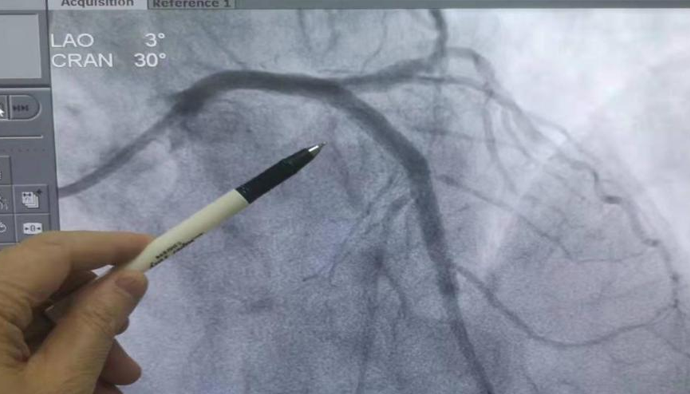

心脏血管开通恢复血流(术后)图示